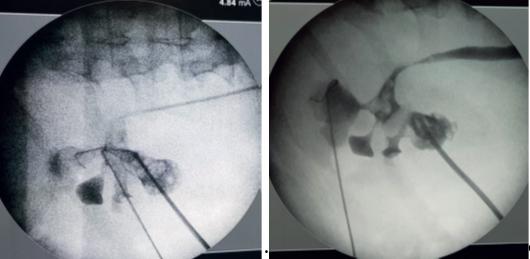

Nefrolitotomia percutanată (NLP) în litiaza coraliformă

2.Nefrolitotomia percutanată standard.

Pacienții preferă o incizie de 1 cm lungime, în comparație cu intervențiile deschise unde rezultatul este o cicatrice greu de acceptat, în special de către femei. (Fig.2)

Intervenția poate fi indicată la pacienții cu un singur rinichi, dar și la pacienții cu litiază renală și insuficiență renală, acestia au însă nevoie de asistență metabolică si un echilibru strict de intrare / ieșire a lichidului de irigare. Poate rezolva și situații speciale, cum ar fi rinichiul în potcoavă, pacienți cu obezitate morbidă, dizabilități locomotorii, rinichi hipermobil, afecțiuni asociate ureterale, pacienți purtători de sonde JJ, a celor cu nefrostomii sau ureterostomii. (Fig.3)

În plus, pacienții sunt mai dispuși să accepte o nefrostomie pentru câteva zile, decât stentul JJ necesar după o ESWL, sau o ureteroscopie flexibilă. Procedura este reproductibilă; prezentăm mai jos un pacient cu cicatrice de pielolitotomie dreaptă și 2 proceduri NLP anterioare. (Fig 3 C)

NLP, principii generale

Rezultatele acestei intervenții miraculoase, dar nu lipsită de riscuri, depind de măsura în care sunt respectate principiile tehnicii și mai ales de modul în care acestea sunt aplicate. Experiența însă, îți poate spune când și cum să faci acest lucru.

Securitatea pacientului trebuie să fie prioritatea majoră pentru practician, iar acest deziderat l-am îmbrățișat pe tot parcursul celor 25 de ani de când fac această intervenție.

Nefrolitotomia percutanată ar trebui să se efectuează numai pe un rinichi funcțional. Strategia depinde de compoziția calculului, dimensiuni, densitate, starea rinichilor, comorbiditățile pacientului, dotarea serviciului și mai ales, de competența câștigată și dovedită într-un centru de excelență de către practician. Orice istoric chirurgical anterior este important.Trebuie apoi ținut cont de contraindicațiile absolute și relative pentru: sarcină, tulburări de sângerare (probleme de coagulare netratate), afecțiuni pulmonare severe, diformități ale coloanei, in-

În situații deosebite, am combinat nefroscopul rigid cu nefroscopia flexibilă. (Fig.4B) Această combinație crează însă o problemă legată de schimbarea camerelor și a surselor de lumină, consumatoare de timp. Pentru a evita acest lucru s-au imaginat nefroscoape multifuncționale, cu teci multifunctionale. (9)

3.Miniperc singur sau combinat cu NLP

În cazuri selective, asociez Miniperc nefrolitotomiei percutanate standard, considerând că o puncție minimă suplimentară, controlată, este mai sigură decât încercarea forțată, necontrolată, de a extrage un calcul dintr-o zonă care nu este accesibilă nefroscopului rigid, NLP pas cu pas

Pregătirea preoperatorie a pacientului trebuie sa fie extrem de minuțioasă în ceea ce privește diagnosticul complet și strategia operatoare. Sunt pași de urmat care cuprind: antibioterapia properatorie (prefer o săptămână la cei infectați), analize obișnuite și specifice în funcție de comorbidități, poziție operatorie, alegerea accesului în rinichi (prefer monoplanar, fluoroscopic), alegerea anesteziei (prefer rahidiană).

Este extrem de importantă analiza preoperatorie a explorărilor (prefer CT și UPG pentru a determina configurația finală a sistemului pielocalicial) care stabilesc dimensiunea, volumul calculului (cu consecințe privind estimarea timpului necesar), identificarea calicelor posterioare (rinichi tip Brodel, Hodson) (Fig 5B), decizia calicelui de puncționat (inferior sau superior), decizia puncțiilor mul-

tiple (superior, mijlociu, inferior), puncția și dilatația via fornix, pentru obținerea unei rate cât mai mari de ’’stone free’’ și toate măsurile necesare pentru evitarea complicațiilor majore. Decizia finală a abordului calicial a fost întotdeauna luată după ureteropielografia retrogradă (Fig.5) și după întoarcerea pacientului în poziția procubit (harta intervenției, Fig.5 C (10)), poziție pe care am folosit-o întodeauna. Uneori, strategia de puncționare adoptată pe baza informațiile imagistice se poate modifica după așezarea pacientului în procubit ventral (rinichiul ascensionează). Sunt încă dispute în literatură legate de poziția pacientului în timpul intervenției. Mă aliniez celor care consideră că, fiecare practician trebuie să folosească tehnica în care a fost instruit, în interesul securității pacientului. (11)

De altfel, este știut că numărul pacienților care au nevoie cu adevărat de poziția în decubit dorsal (supine), este la fel de mic ca și numărul pacienților pentru care poziția procubit ventral este contraindicată. La fiecare pacient se poate elabora un scor de dificultate, în funcție de duritatea calculului (unități Haunsfild), de volumul calculului (între 5000-20000 și peste 20000 mm cubi) și de favorabilitatea calicelui ce urmează a fi puncționat.

De cele mai multe ori, în litiaza coraliformă calculii blochează calicele, făcând dificil accesul în infundibul spre bazinet, fiind nevoie de o negociere a ghidurilor cu calculii din calice.

Dilatarea traiectului am efectuat-o întotdeauna cu dilatatoarele metalice Alken la nivelul calicelui, pentru evitarea lezării infundibulului și a bazinetului. Dilatarea se face sub control fluoroscopic, cunoscând riscul de pierdere a traiectului. Li-

totriția cea mai des folosită este cu energie ultrasonică, ce permite și aspirația, un element foarte important în economia intervenției. Drenajul cavităților l-am făcut cu una sau mai multe nefrostomii, iar drenajul hemostatic, când a fost cazul, cu cateter Foley. Urină prelevată din pielonul afectat și fragmente litiazice extrase sunt trimise pentru culturi și antibiogramă la sfârșitul intervenției. La externare, le recomandăm pacienților analiza calculilor, pentru a completa tratamentul și a preveni recidivele. Pentru securitatea pacientului am mers pe (când a fost necesar) decizia de a efectua intervenția în doi timpi. (Fig.6)

Puncția calicială multiplă

Mai multe tracturi sunt decise și individualizate pentru fiecare pacient în momentul intervenției chirurgicale. Pentru controlul și securitatea intervenției, puncțiile trebuie efectuate la începutul intervenției și asigurate cu ghiduri de așteptare. Sunt multe studii în literatură, pro și contra, legate de riscul de sângerări intra și postoperatorii. (Fig.5)

Ghidurile AUA sugerează că mai multe tracturi sunt eficiente și sigure în litiaza coraliformă, cu o rată de ’’stone free’’ de 79% și o rată de complicații imediate de 15%. (13)